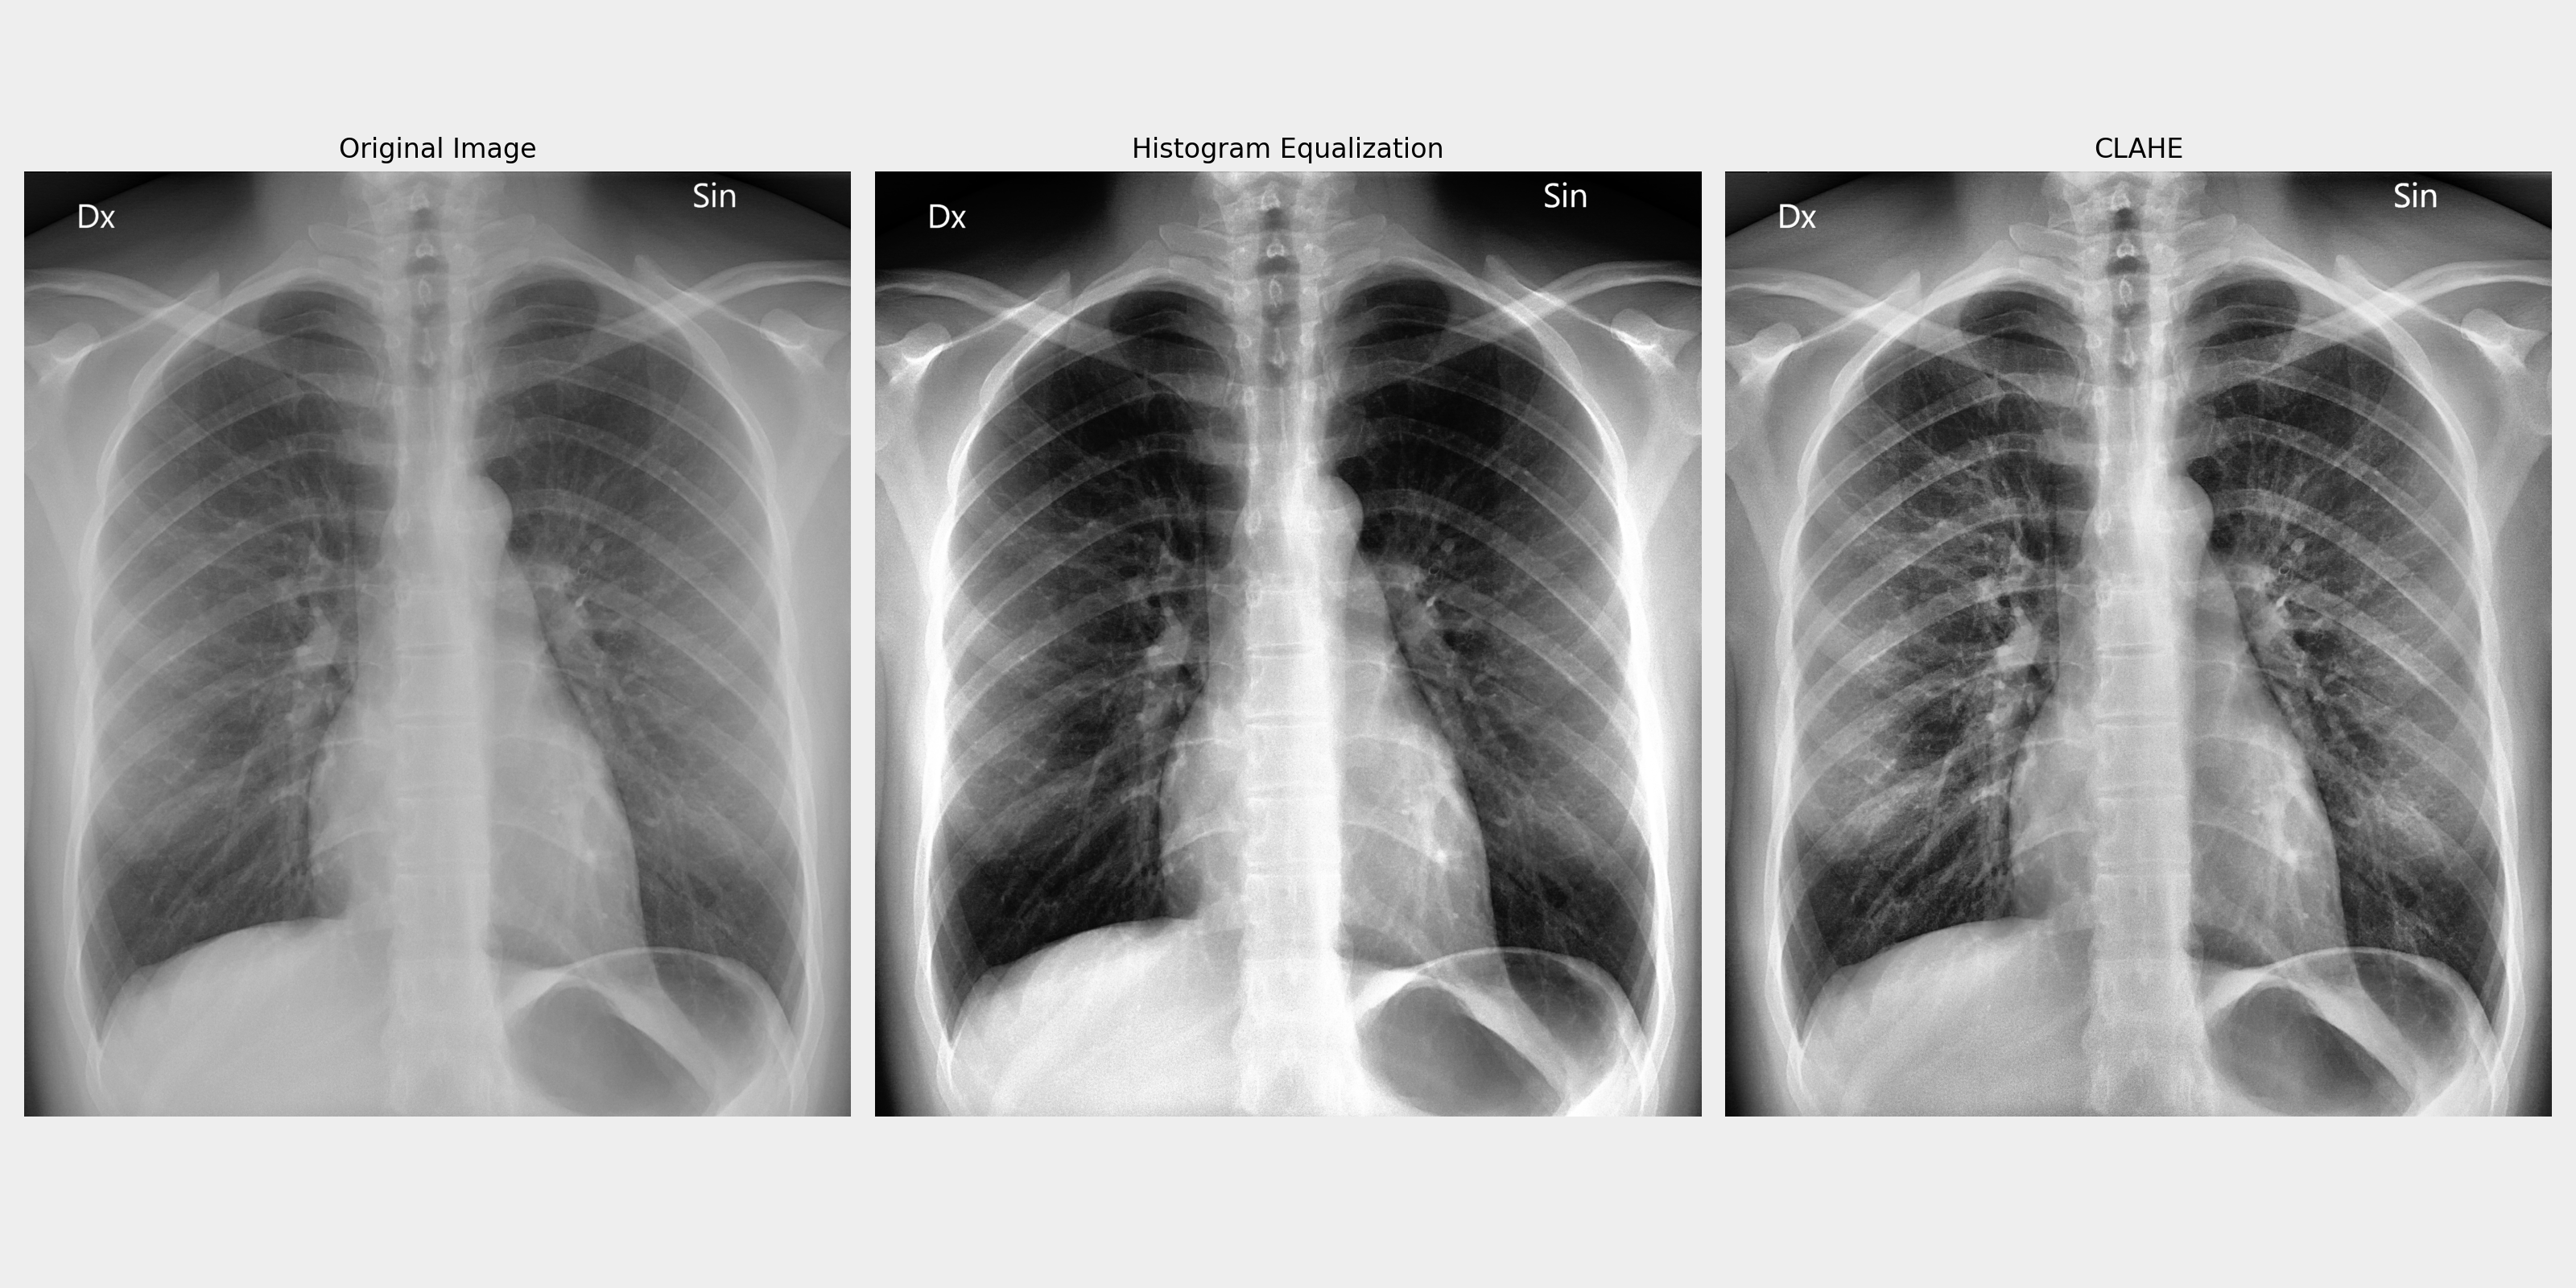

3. CLAHE (Contrast Limited Adaptive Histogram Equalization)

기본 히스토그램 평활화(Histogram Equalization)는 이미지 전체에 대한 히스토그램을 평활화하여 명암을 균일하게 만들어주지만, 이는 이미지의 세부적인 부분에서 지나치게 강한 대비 변화가 생길 수 있는 단점이 있습니다. 반면, CLAHE(Contrast Limited Adaptive Histogram Equalization)는 이미지를 작은 타일로 분할한 후 각 타일에서 히스토그램을 개별적으로 평활화하기 때문에, 국부적(local)인 대비를 개선할 수 있습니다. CLAHE는 특히 이미지의 어두운 영역이나 밝은 영역이 과도하게 강조되는 문제를 해결하는 데 유리합니다. 또한, 대비 한계(Contrast Limiting)를 적용하여 너무 많은 픽셀 값이 같은 구역에 몰리는 것을 방지하고, 이미지의 노이즈나 인공적인 부분이 두드러지지 않도록 제어합니다. CLAHE는 주로 의학 이미지(예: X-ray), 인공위성 이미지 등에서 세부적인 대비를 강조해야 하는 상황에서 자주 사용됩니다.

import cv2

import numpy as np

import matplotlib.pyplot as plt

# Load image (convert to grayscale image)

image = cv2.imread('resources/x-ray.jpg', cv2.IMREAD_GRAYSCALE)

# Apply basic histogram equalization

equalized_image = cv2.equalizeHist(image)

# Apply CLAHE

clahe = cv2.createCLAHE(clipLimit=2.0, tileGridSize=(8, 8))

clahe_image = clahe.apply(image)

plt.figure(figsize=(12, 8))

plt.subplot(1, 3, 1)

plt.imshow(image, cmap='gray')

plt.title('Original Image')

plt.axis('off')

plt.subplot(1, 3, 2)

plt.imshow(equalized_image, cmap='gray')

plt.title('Histogram Equalization')

plt.subplot(1, 3, 3)

plt.imshow(clahe_image, cmap='gray')

plt.title('CLAHE')

plt.tight_layout()

plt.show()